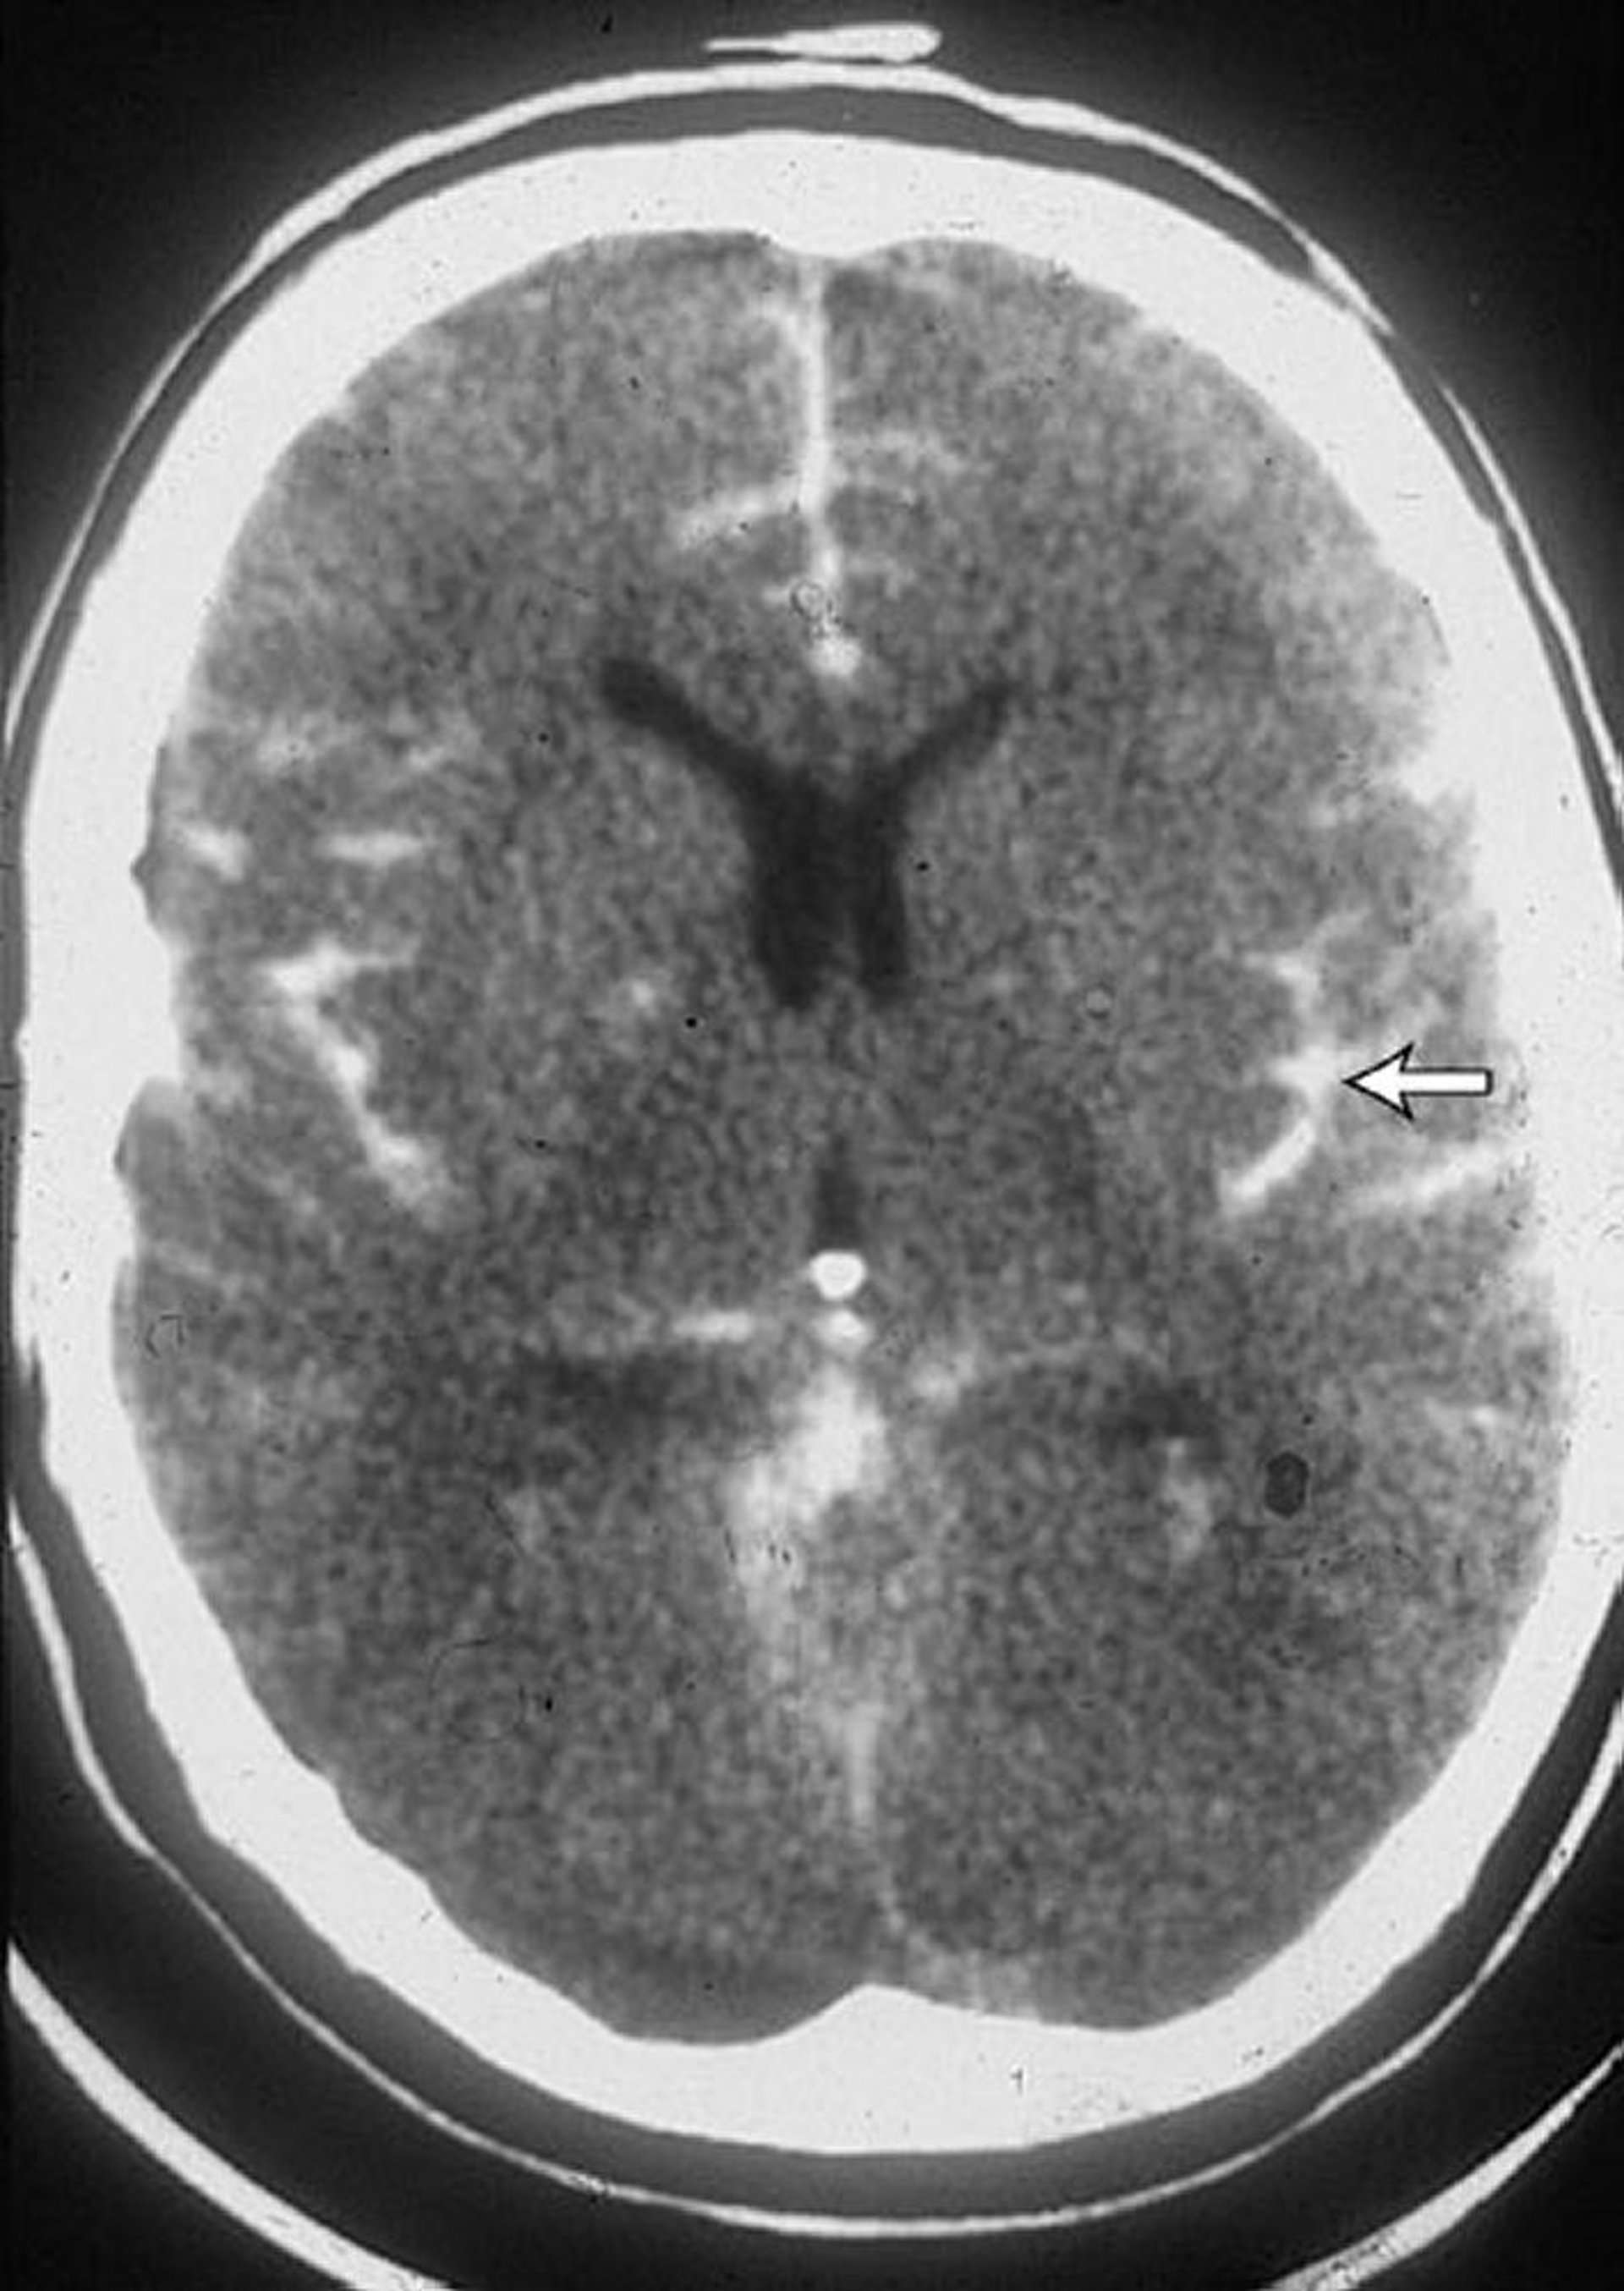

くも膜下出血

これはくも膜下出血患者のCTであり,脳溝内に血液がみられる(矢印)。血液はしばしば脳室内にもみられる。